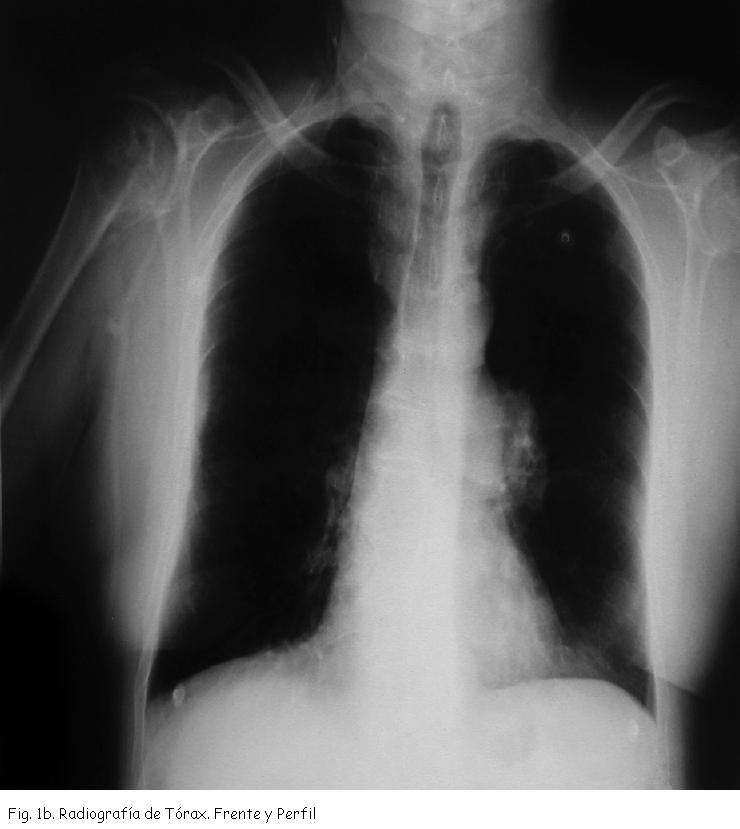

Radiografía de tórax muestra opacidad redondeada de contornos bien delimitados a nivel hiliar izquierdo.(Figura 1a, 1b)